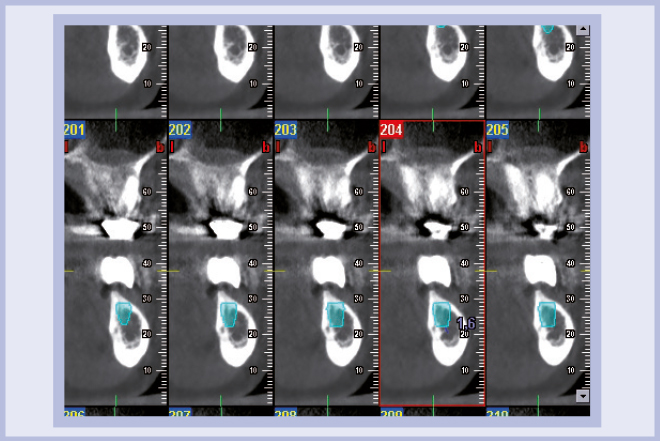

Per riabilitare la masticazione del terzo quadrante, con osso gravemente atrofico, si procede allo studio del caso con esame radiologico 3D e posizionamento virtuale di impianti Exacone® Leone. La prima valutazione è stata eseguita con il software dell’apparecchio radiografico Cone Beam presente in studio. Dopo aver verificato che la quantità di osso residuo fosse sufficiente all’inserimento di due impianti, seppur di dimensioni ridotte, in sede 3.5 e 3.6 senza l’ausilio di tecniche di rigenerazione ossea (Figg. 1-3), si richiede al laboratorio di confezionare una mascherina radiologica con ceratura diagnostica radiopaca e repere standardizzato a livello incisale come da protocollo Leone (Figg. 4, 5). Si verifica quindi clinicamente l’assenza di mobilità della mascherina dopo il posizionamento nel cavo orale del paziente (Figg. 6, 7). Si effettua una CBCT con la mascherina in posizione e l’esame viene inviato in formato DICOM all’azienda Leone assieme al modello master della paziente. L’azienda provvede quindi ad inviare agli Autori il software 3Diagnosys (software di progettazione) in licenza monopaziente con caricati i file DICOM ricevuti; il software viene quindi utilizzato per la progettazione definitiva del caso (Figg. 8-12).

- Figg. 1-3 – Esame Cone Beam iniziale, si verifica la fattibilità di inserimento impianti

- Fig. 2 mento impianti

- Fig. 3